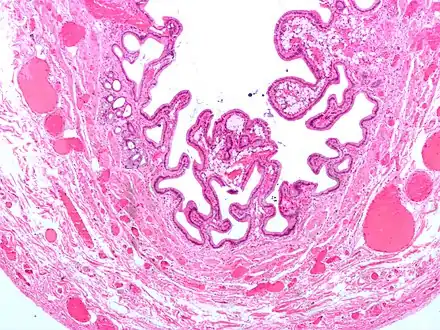

Cholesterolosis of gallbladder

In surgical pathology, strawberry gallbladder, more formally cholesterolosis of the gallbladder and gallbladder cholesterolosis, is a change in the gallbladder wall due to excess cholesterol.[1]

The name strawberry gallbladder comes from the typically stippled appearance of the mucosal surface on gross examination, which resembles a strawberry. Cholesterolosis results from abnormal deposits of cholesterol esters in macrophages within the lamina propria (foam cells) and in mucosal epithelium. The gallbladder may be affected in a patchy localized form or in a diffuse form. The diffuse form macroscopically appears as a bright red mucosa with yellow mottling (due to lipid), hence the term strawberry gallbladder. It is not tied to cholelithiasis (gallstones) or cholecystitis (inflammation of the gallbladder).[2]